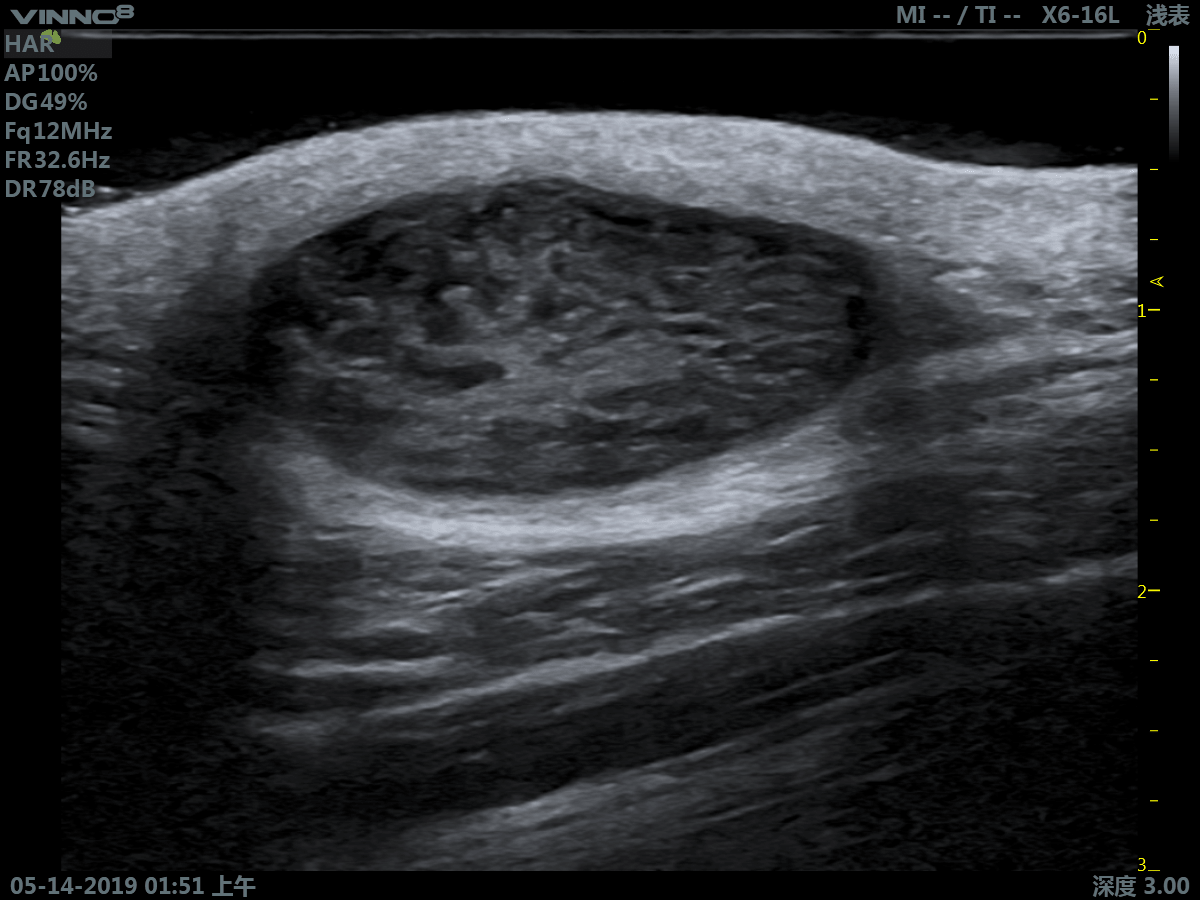

- мелкие объекты (включая щитовидную железу, молочную железу, семенники и т.д.)

3. Режим тканевой гармоники - технология выделения гармонической составляющей колебаний внутренних органов, вызванных прохождением сквозь тело базового ультразвукового импульса.

6. SPECKLE NOISE REDUCTION. Функция фильтрации спекл-шума – «зернистости» ультразвукового изображения